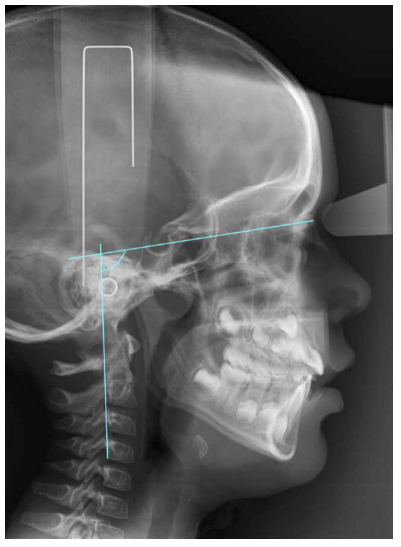

Otra variable estudiada fue CVT-SN, ángulo que se forma entre SN y la línea que recorre el punto póstero-superior y punto póstero-inferior de las cuatro vértebras cervicales (Figura 2).